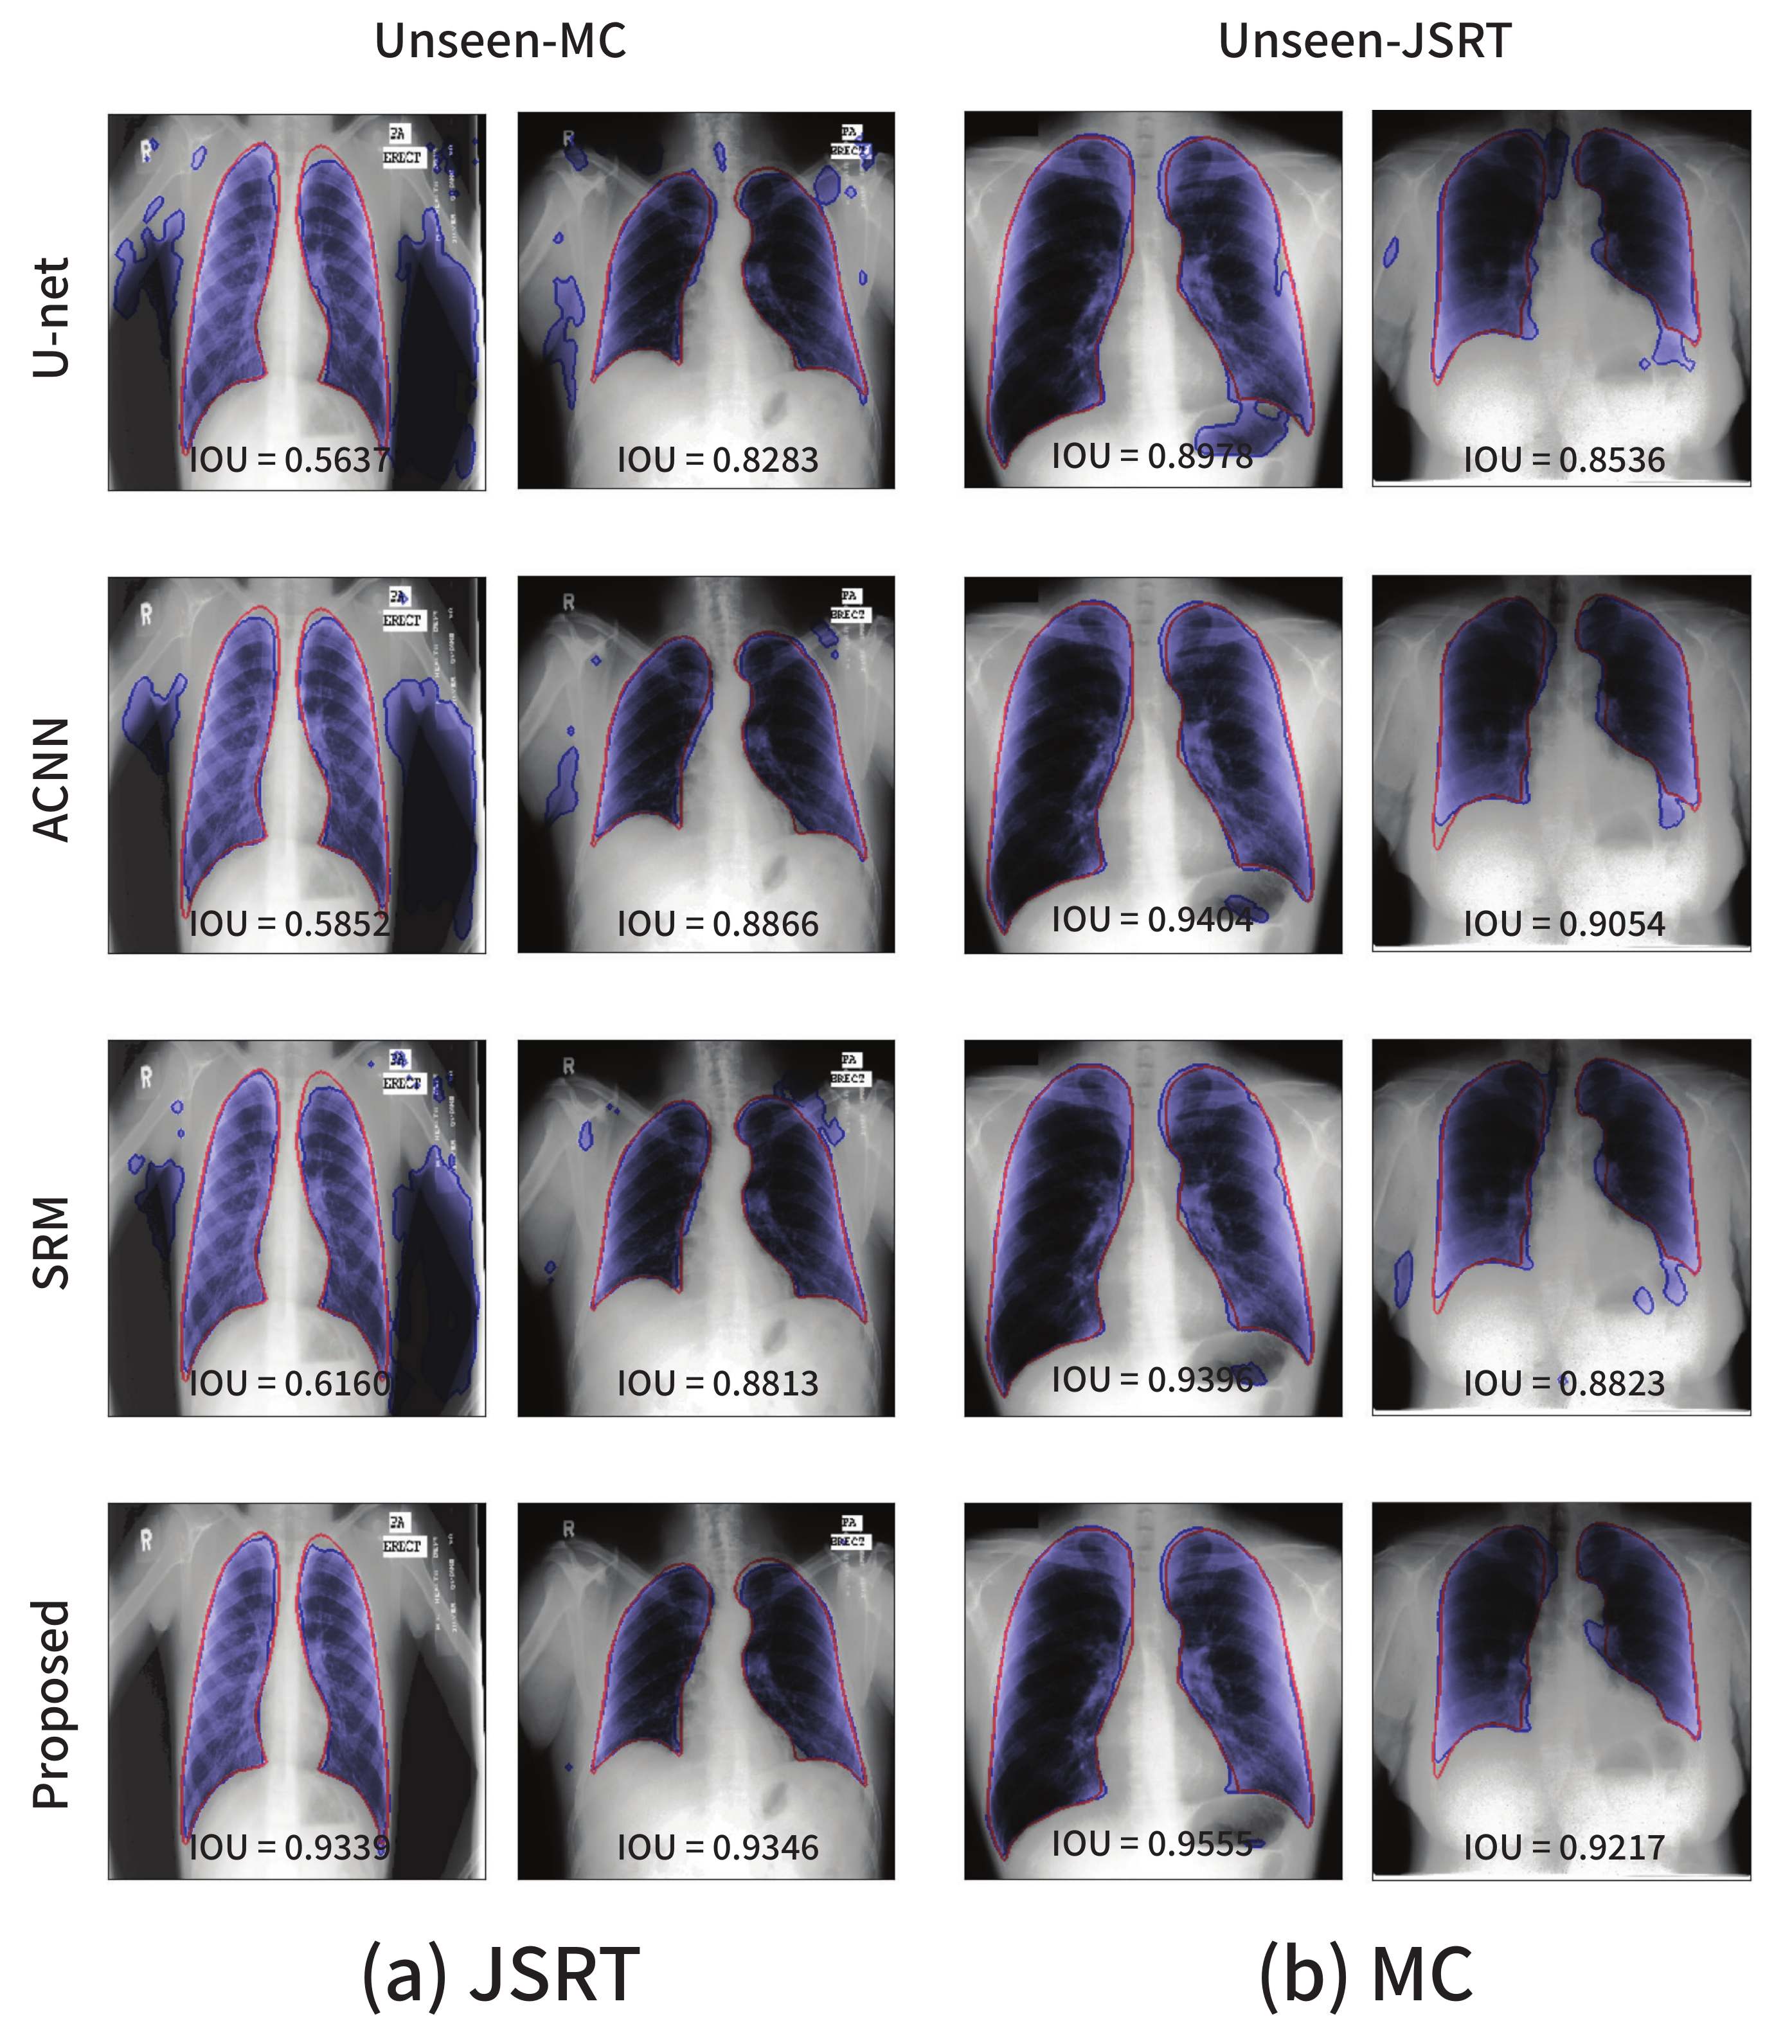

4.5. Domain Robustness

Learning the anatomical structures in medical images can enhance several aspects of segmentation models, for instance, in the form of domain robustness. To demonstrate the domain robustness of the proposed method, we trained a segmentation network by using images from a single source (i.e., domain) and tested the trained model by using images from other sources. For example, the JSRT dataset was used for training, and the trained model’s performance was evaluated using the MC dataset in the case of the lung segmentation task. In general, if a network exhibits a high performance on datasets from unseen domains, the network is considered to be robust to domain shifts. We conducted similar experiments using the spinal cord dataset: images from each site, site2, site3, and site4, were used as the training images, and the segmentation performance was examined on images corresponding to other domains. Images from site1 were utilized only for testing because the dataset for site1 contains excessively few images to be used for training. The trained models in the previous experiments were used to examine their robustness to domain shifts.

The domain robustness (i.e., domain generalization) performance of the segmentation models in the lung segmentation task is summarized in Table 6. Two experimental settings were considered, JSRT→MC and MC→JSRT. In particular, JSRT→MC corresponds to the segmentation performances on the MC dataset for a model trained on the JSRT dataset. The last row presents the average performance over the two settings. The models trained using the proposed strategy exhibit superior performances in terms of both the overlap and distance measures, which indicates that the proposed method not only enhances the segmentation performance on the source domains, but also renders a segmentation model more robust to domain shifts. As can be seen in Figure 3, although the visual characteristics of the two datasets are considerably different, the experimental result highlights that the domain generalization performance of CNN-based segmentation models can be enhanced if we carefully design a training framework for the model to learn the anatomical structure information related to the given tasks.

Table 6.

The visualizations of several segmentation results are presented in Figure 6. The red solid line and blue shaded area represent the ground-truth and segmentation outputs, respectively. The existing approaches including the baseline U-Net are sensitive to even a small degree of domain shift, and this phenomenon cannot be simply resolved by applying data augmentation techniques such as random adjustments of the brightness and contrast.

Figure 6.

Segmentation results on the lung segmentation task obtained from the models trained using the (a) JSRT and (b) MC datasets, respectively. The blue color represents the segmentation results, and the ground-truth is in red.